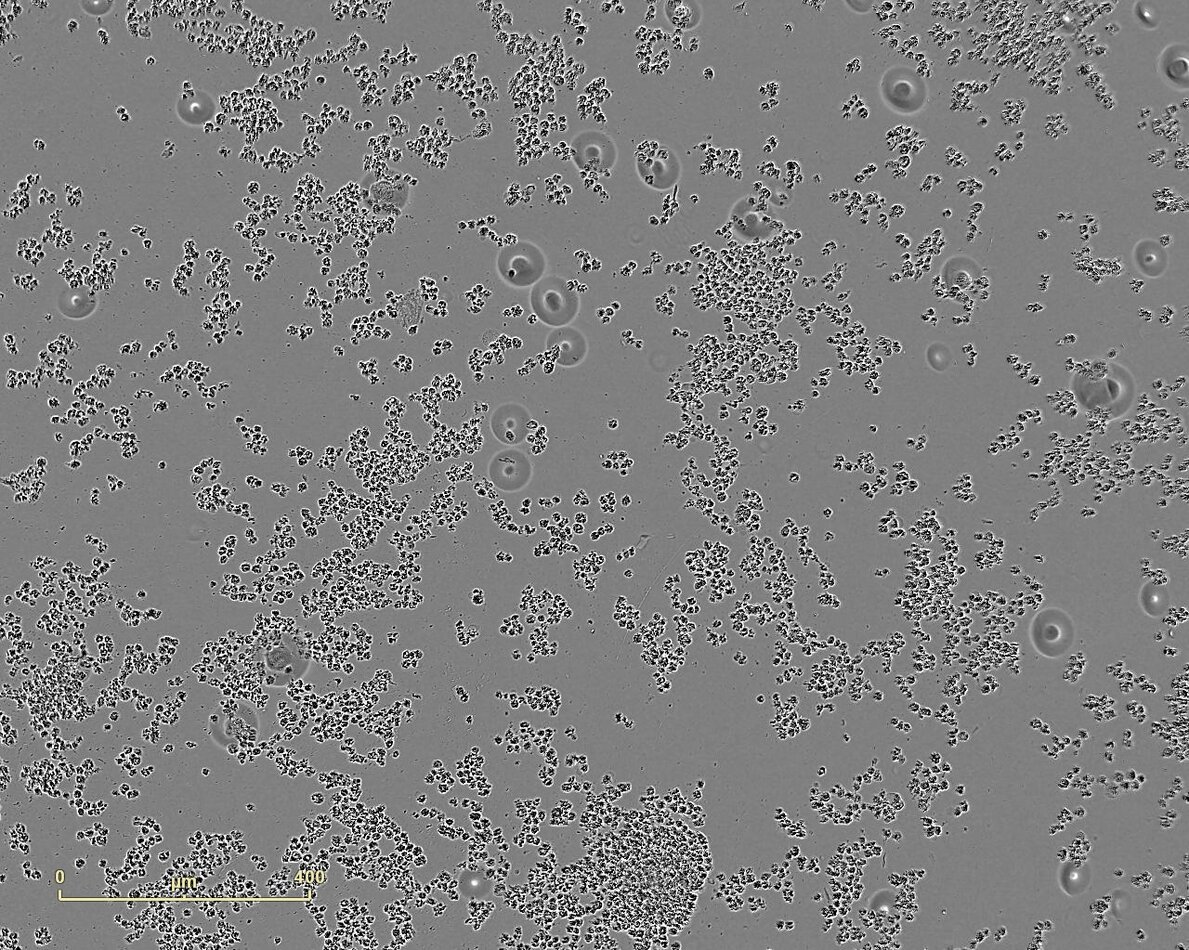

The study of the cytotoxicity of a compound having a modulating activity on the response of the cells is essential.

It allows to verify that the active molecule does not induce any modification of the cell viability compared to untreated cells.

Several cell lines are available at PCBIS for the study of cytotoxicity.